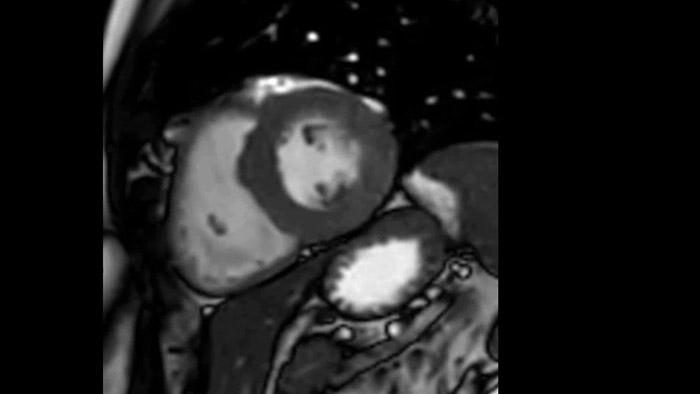

Diagnostic and prognostic utility of cardiac MR is increasing. Assess the anatomy and function of the heart using cine acquisitions, acquire information about perfusion and viability of the cardiac tissue, visualise potential edema with black blood sequence, access and even quantify tissue characterisation with CardiacQuant.

Due to the design of the BlueSeal magnet there is a negligible energy transfer from gradient coil to the magnet. This allows to maintain perfect B0 stability overtime which is especially beneficial for B0 sensitive acquisitions like cardiac bTFE sequences.

Addition of Compressed SENSE to your cardiac exams reduces the time spent in the MRI scanner for the patient and enables the reduction of breath hold times while maintaining virtually equal image quality4. Compressed SENSE is applicable to both 2D and 3D acquisitions.